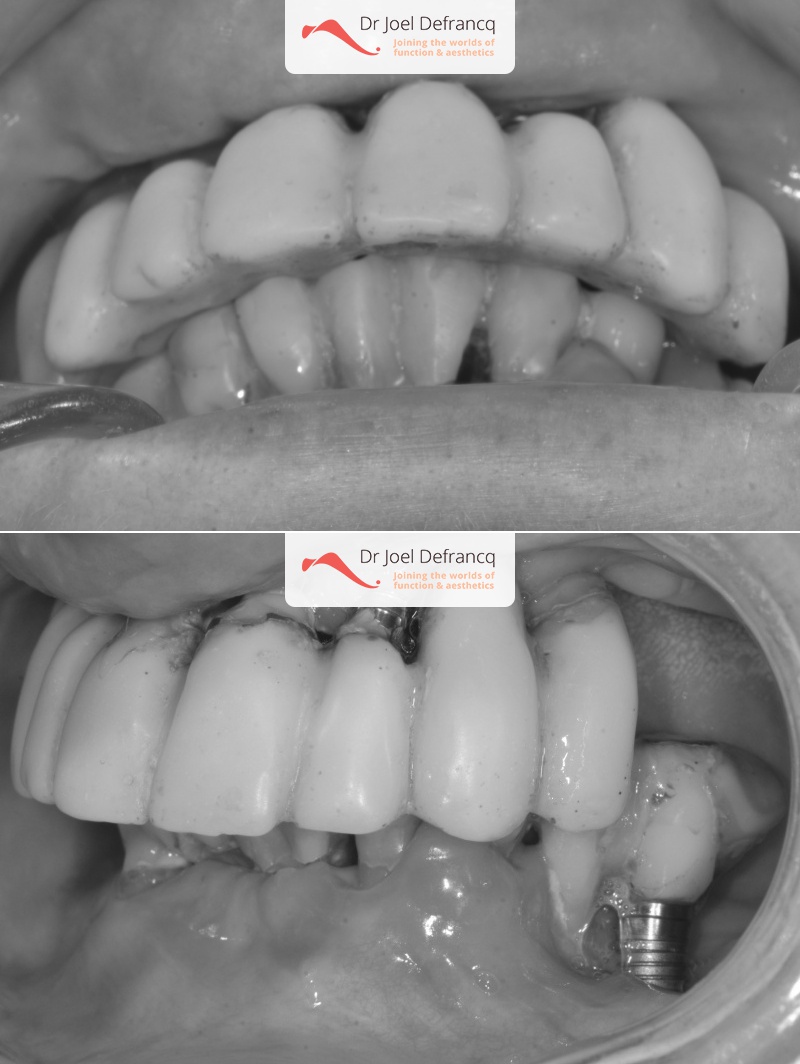

Kait: new teeth in a week - 4 zygoma implants

Behandeling tandheelkundige implantaten

- Vaste tanden op implantaten (bovenkaak)

- Vaste tanden op implantaten (onderkaak)